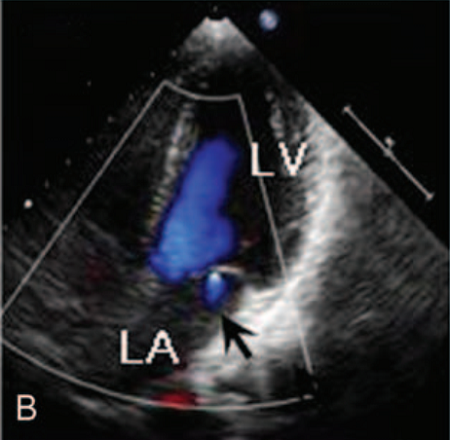

青年男性,34岁,反复胸部针刺样疼痛及头晕1年。除低血压和"神经衰弱"之外,既往无特殊病史,不抽烟、酗酒,无心脏病家族史。患者年轻的时候身体虚弱。入院时血压110/70 mmHg,心率72次/分,体检无特殊。心电图和胸部X光显示正常。但超声心动图却有重大发现,提示左心室壁乳头肌水平以下小梁增加,心内膜壁深层交界凹陷,特别是在心尖部游离壁(图A),其小梁厚度为9mm,心肌变得更薄;心尖搏动减弱,二尖瓣见血液反流(图B),LVEF 57%。冠脉CTA显示左前降支(LAD)心肌桥,长度为38.9 cm(图C、D),余冠脉未见明显异常。

图B 二尖瓣见血液反流